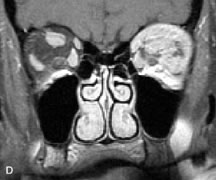

Extraocular muscle enlargement in patients with thyroid-associated orbitopathy is demonstrated equally well with CT and MRI studies. However, the superior tissue contrast on MR images reveals better details of the relationships of the optic nerve to the thickened muscles at the orbital apex (Fig. 16).50 In addition, MRI may be able to differentiate between muscles that are enlarged as a result of edema and active inflammation and those enlarged because of fibrosis by their T2 relaxation times.21 Quantitative MRI was not found to be accurate in predicting the success of low-dose orbital irradiation.51 However, a muscular index relating the diameters of the rectus muscles to the bony orbital dimensions was useful in predicting optic nerve compression.52

Fig. 16. A-C, T1-weighted MR scans obtained with a high-resolution surface coil demonstrate fusiform enlargement of the extraocular muscles. The medial, lateral, and inferior rectus muscles are especially involved. Note the relative sparing of the tendinous insertions, a finding characteristic of this disease process, as well as fatty infiltration of the lateral and inferior rectus muscles. There is marked proptosis, best visualized on the sagittal image (A), and mild crowding of the optic nerve at the orbital apex.